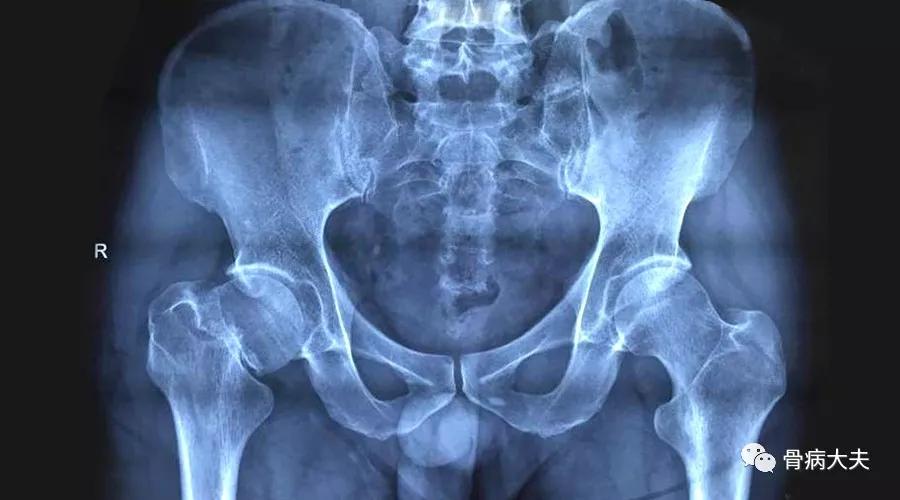

众所周知,股骨头病变坏死,治疗困难,一旦患上这种病,就基本与致残、致瘫不远了。

其实这是一个误区,可怕难治的不是股骨头坏死,而是股骨头坏死晚期。

这就意味着,只要发现的早,治疗的早,股骨头坏死是可以治愈的。

1.股骨头坏死的早期症状

股骨头坏死的早期有五大主要症状,这五大主要症状分别是下肢无力、下肢畏寒、腰部疼痛、臀部疼痛、膝关节部疼痛。